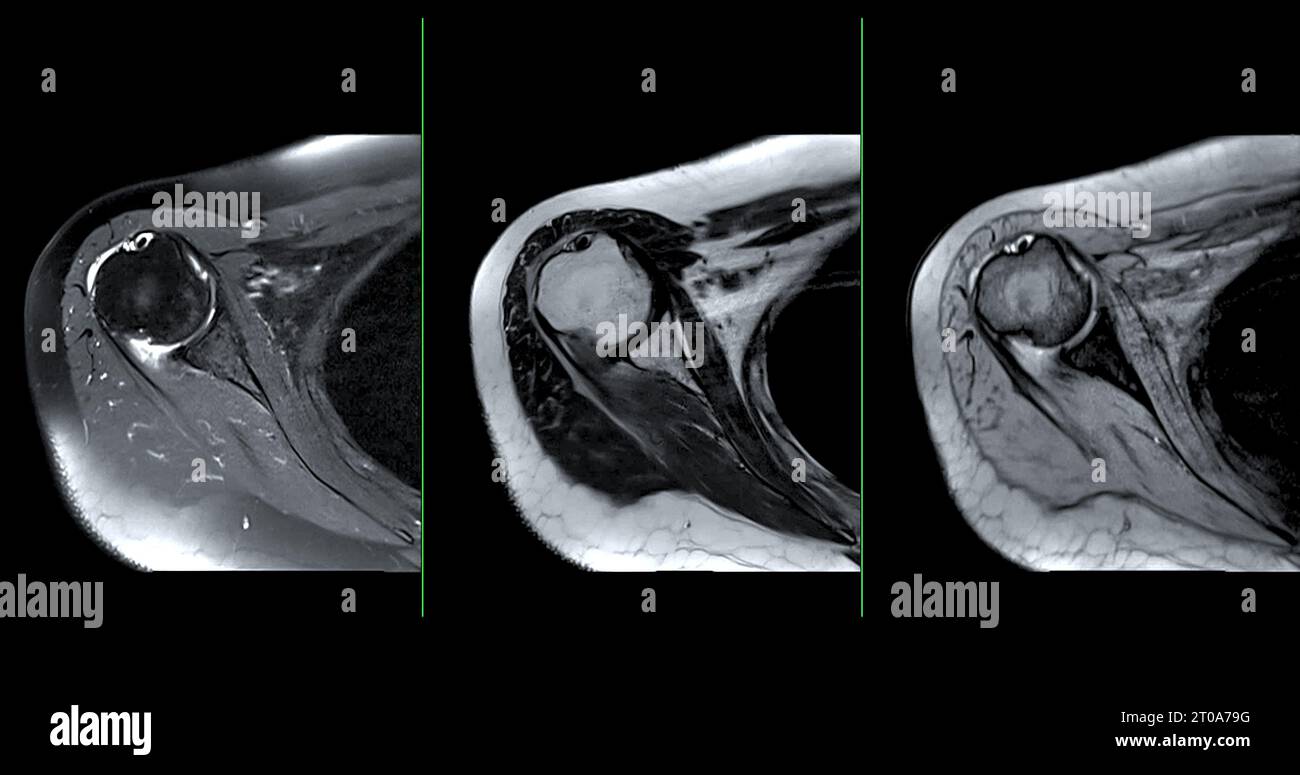

Shoulder imaging Body Bones, Ct Scan, Frozen Shoulder, Shoulder Joint, Physio, Clinic, Medicine What Can Mri Of Shoulder Detect magnetic resonance imaging (mri) of the shoulder is done to: The mri allows accurate assessment of. what can a shoulder mri diagnose? Learn more about what it’s for,. the evaluation of the shoulder, and especially its soft tissue structures, is best done with an mri. magnetic resonance imaging (mri) of the shoulder uses a powerful magnetic. What Can Mri Of Shoulder Detect.

What Can Mri Of Shoulder Detect . magnetic resonance imaging (mri) of the shoulder uses a powerful magnetic field, radio waves and a computer to produce. a shoulder mri is a test that uses a magnetic field to take pictures of your shoulder. The mri allows accurate assessment of. in particular, the images include your muscles, ligaments, and cartilage as well as any other components. magnetic resonance imaging, or mri, uses a magnet to examine the inside of your body, useful for diagnosing shoulder pain and. magnetic resonance imaging (mri) of the shoulder is done to: what can a shoulder mri diagnose? the evaluation of the shoulder, and especially its soft tissue structures, is best done with an mri. Learn more about what it’s for,. A shoulder mri can diagnose tears of the rotator cuff, labrum, and tendons.